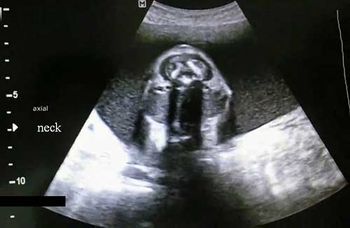

Challenge your diagnostic skills: Can you identify the condition causing the abnormality seen in these images of the fetal neck?